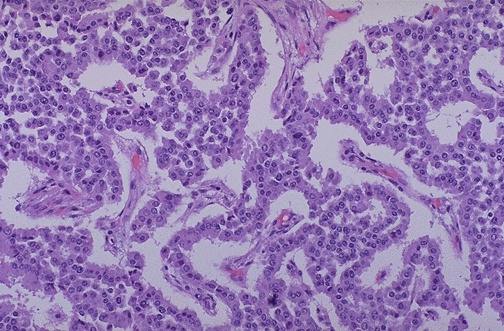

The neoplastic cells of the islet cell adenoma at high magnification demonstrate very little pleomorphism. Note the vascularity of this neoplasm, similar to normal islets. Such neoplasms may be small and detected only by their hormonal output.